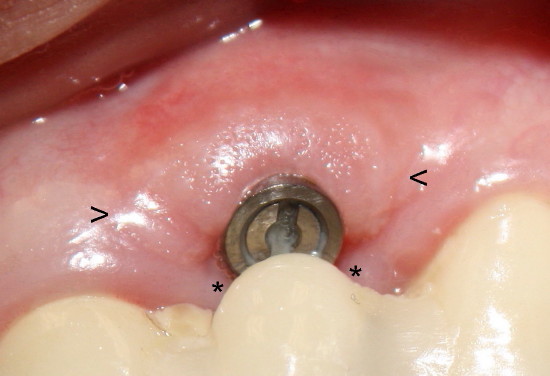

Three weeks post-operatively, a thick band of gingiva with stippling forms in the labial aspect of the implant (between arrowheads in Fig.5, as compared to the gingiva in the edentulous region pre-operatively in Fig.6). In addition, the gingiva is also closing the wound in the lingual aspect the implant (* in Fig.5), back to main article